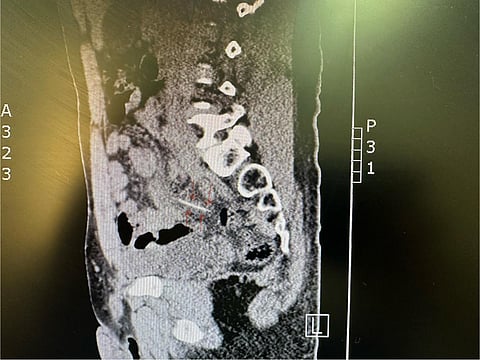

وتفصيلًا: حضر المريض إلى قسم الطوارئ وهو يشكو من آلام في البطن، وبعد الفحص السريري والإشعاعي تبيّن وجود عود تنظيف الأسنان خارجًا من نهاية الأمعاء الدقيقة؛ ما أدى إلى ثقب صغير داخلها.

وقرّر الفريقُ الطبي المختصّ إجراءَ عملية استكشافية بالمنظار الجراحي، وتمت إزالة عود تنظيف الأسنان الذي يبلغ طوله 7 سم، ونجح الفريق الطبي في إغلاق الثقب الذي أحدثه العود في الأمعاء الدقيقة؛ حيث تكلّلت العملية النوعية التي أجريت عن طريق المنظار الجراحي بالنجاح ولله الحمد، وتم وضع المريض تحت الملاحظة لمدة ثلاثة أيام، ومن ثَمّ غادر المستشفى وهو بصحة جيدة.